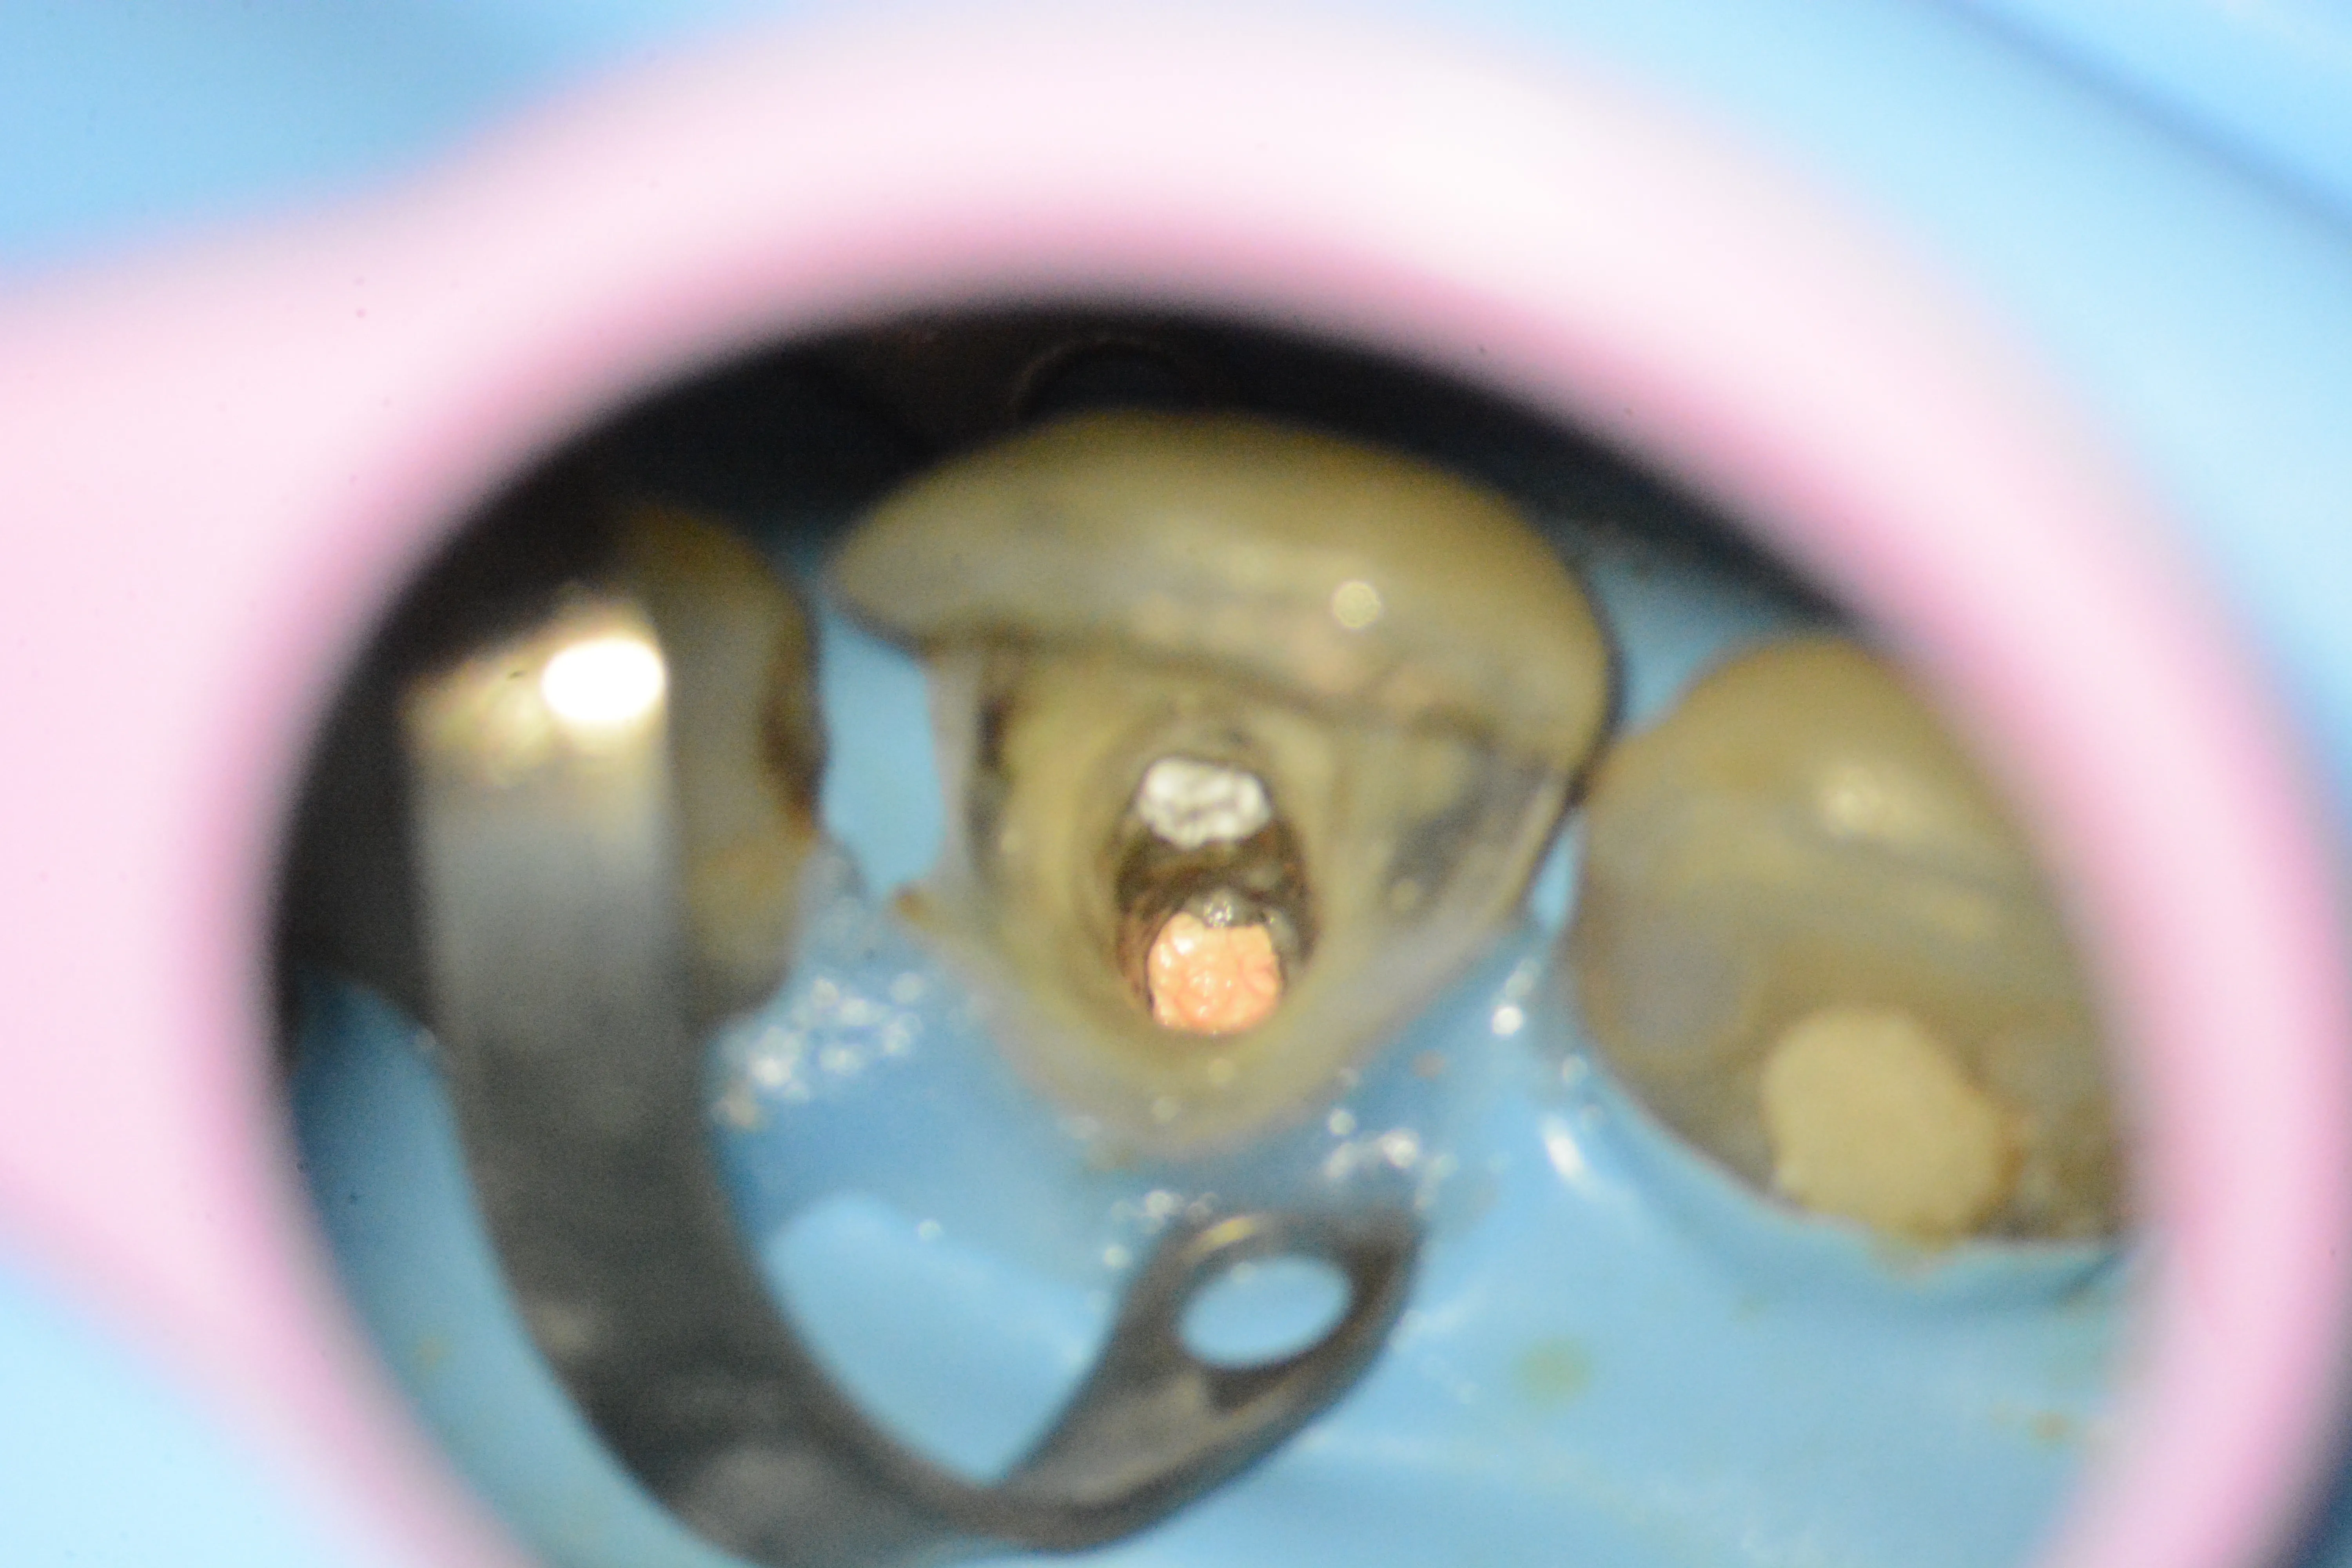

2 – Aspectul pivotului metalic dupa îndepărtarea parțială a materialului de build-up

3 – Aspectul pivotului metalic după eliberarea din partea coronară și resturi de ciment cu carie secundară